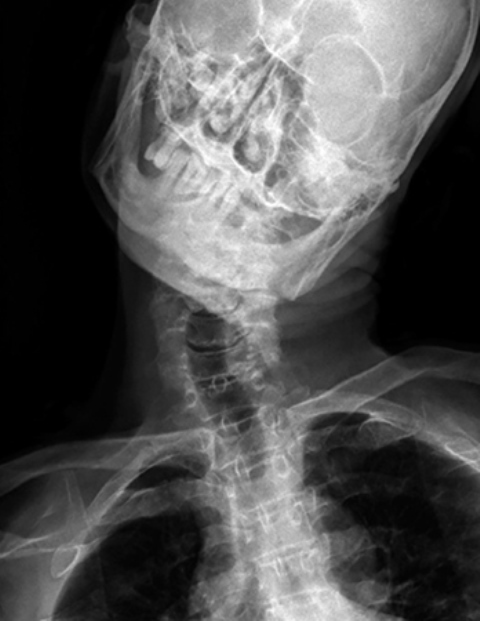

ب) دنده گردنی چیست؟

گاهی اوقات پایینترین مهره گردن یعنی مهره هفتم هم یک دنده دارد که البته به اندازه دنده های سینه ای نیست و از آنها کوچکتر است. پس این دنده در بالای دنده اول سینه ای قرار میگیرد. به این دنده اضافی دنده گردنی میگویند و از هر 200 انسان در یک نفر وجود دارد. پس این انسان ها بجای 12 جفت دنده 13 جفت دنده دارند. وجود دنده گردنی ممکن است باعث ایجاد درد در گردن و دست و بیحسی یا مور مور شدن دست شود. دنده گردنی میتواند در یک طرف گردن باشد و یا میتواند دو طرفه باشد . همانطور که گفتیم یک سر این دنده به مهره هفتم گردنی متصل شده است ولی سر دیگر آن معمولا آزاد است. البته گاهی اوقات سر دیگر آن با دنده اول سینه ای مفصل میشود و یا گاهی اوقات از سر این دنده گردنی یک نوار بافتی محکم خارج شده و به دنده اول متصل میشود .

اهمیت این فضای توراسیک اوتلت در بیماری است که به علت تنگ شدن این فضا ایجاد شده و به آن سندرم توراسیک اوتلت Thoracic outlet syndrome میگویند. این فضا به علل مختلفی میتواند تنگ شود. تنگ شدن آن معمولا در طرف راست یا چپ است ولی میتواند دو طرفه هم باشد. بدنبال تنگ شدن این فضا اعصاب شبکه بازویی تحت فشار قرار میگیرند و فشار به این اعصاب، علائمی را برای بیمار ایجاد میکند. گاهی هم ممکن است شریان یا ورید ساب کلاوین هم در این فضا گیر کنند که فشار به آنها هم میتواند علائم دیگری را برای بیمار ایجاد کند

اهمیت دنده گردنی اینست که وجود آن یکی از شایعترین علل ایجاد سندرم توراسیک اوتلت است .

یکی از علل شایع تنگ شدن فضای توراسیک اوتلت، وجود دنده گردنی است. پس اهمیت دنده گردنی اینست که میتواند فضای توراسیک اوتلت را تنگ کرده و به اعصاب یا عروقی که از این ناحیه عبور میکنند فشار ایجاد کند. البته اینطور نیست که هر کسی که دنده گردنی دارد این مشکلات را هم داشته باشد. از هر ده نفری که دنده گردنی دارند فقط در یک نفر آنها به اعصاب یا عروق فشار وارد شده و مشکل دار میشوند .

.jpg)

در بعضی افراد یک نوار بافتی محکم از نوک زائده عرضی مهره هفتم گردنی خارج شده و به دنده اول سینه میچسبد. این نوار بافتی در فضای توراسیک اوتلت است و میتواند مانند دنده گردنی به اعصاب و عروق فشار وارد کند. گاهی اوقات هم فقط زائده عرضی مهره هفته گردنی بلندتر از معمول بوده و در فضای مورد نظر به عروق و اعصاب فشار وارد میکند .